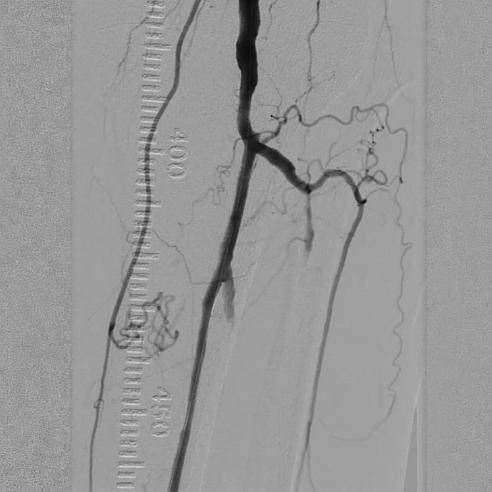

术后评估

造影显示:胫腓干动脉血流恢复通畅,支架形态及位置理想,胫后动脉显影较术前明显改善;

腔内超声证实:铁支架完全张开、贴壁良好,无明显残余狭窄。